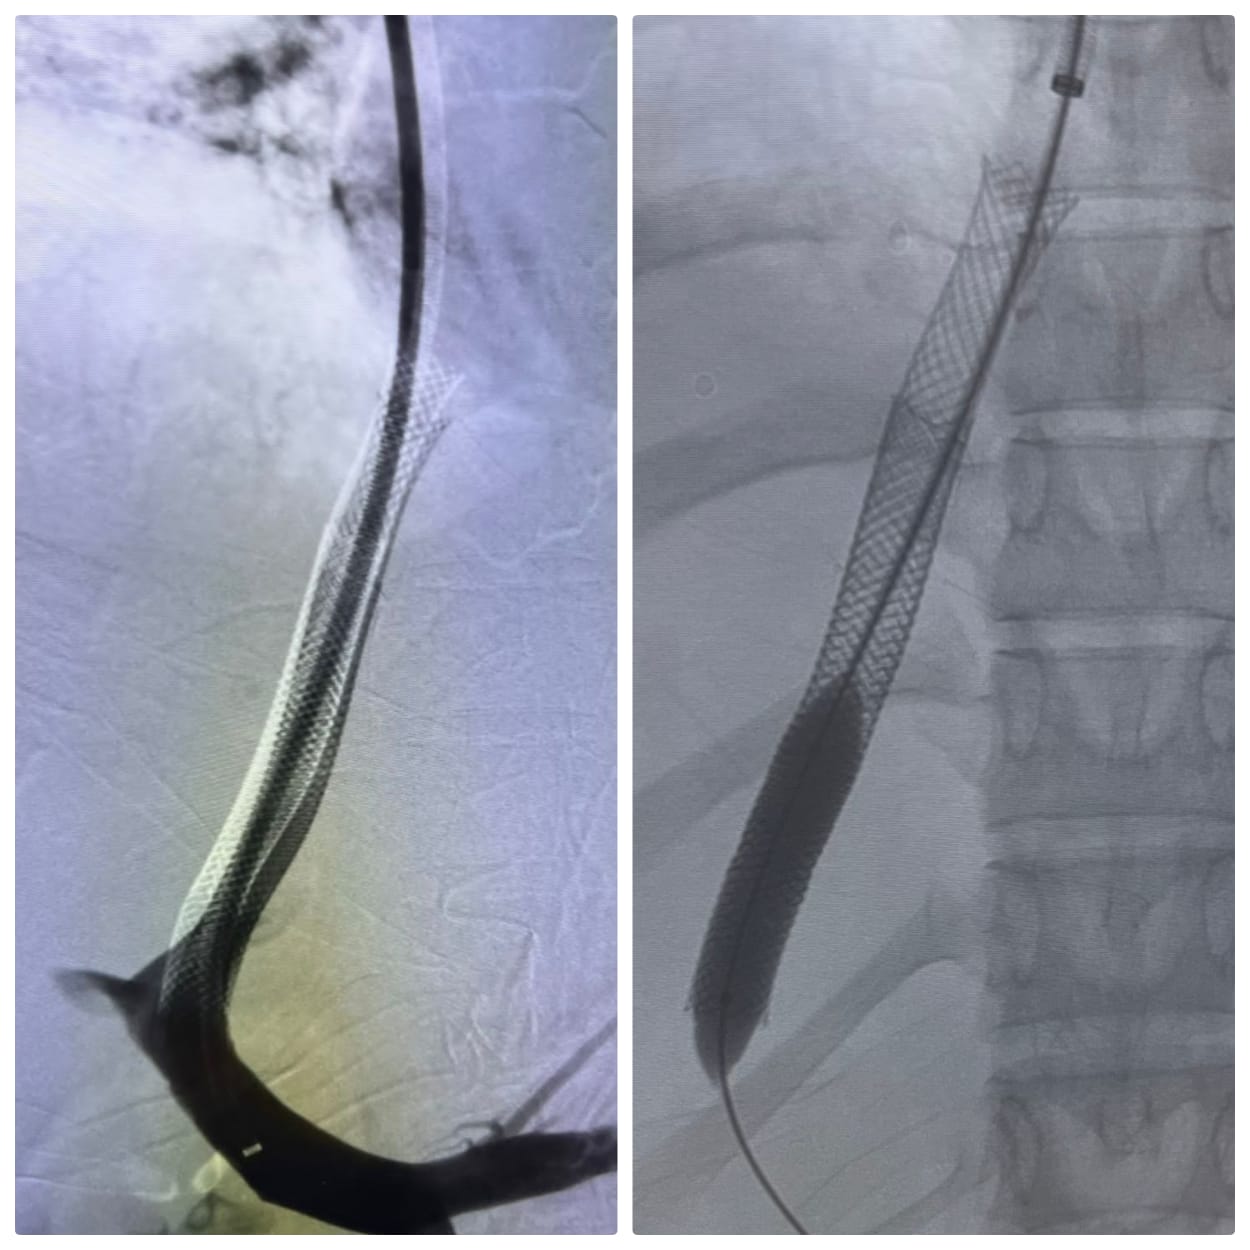

قام الفريق الطبي بإجراء عملية دقيقة لتركيب دعامات معدنية بين الوريد الأجوف السفلي والوريد البابي الكبدي باستخدام تقنية الـ (TIPSS)، والتي تُعد خياراً علاجياً متقدماً  ينفرد به مستشفى الراجحي كونه المركز الوحيد في صعيد مصر الذي يقدم هذه التقنية التي تتطلب مهارة ودقة فائقة وتجهيزات طبية خاصة.

صور الخبر